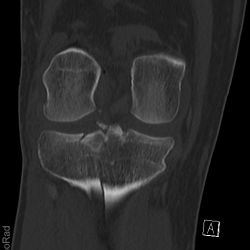

Tibiakopffraktur (nicht disloziert)